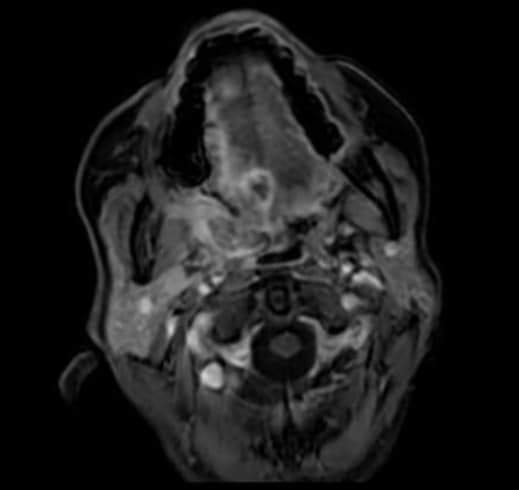

Al igual que la TC (tomografía computada), las imágenes por resonancia magnética muestran imágenes detalladas de los tejidos blandos del cuerpo. Utilizan ondas de Radio e imanes potentes en lugar de rayos X. Debido a que provee una imagen detallada, puede que se haga una Resonancia Magnética para determinar si hay propagación de cáncer en el cuello.

- Resonancia Magnética de Cuello 6 julio, 2022